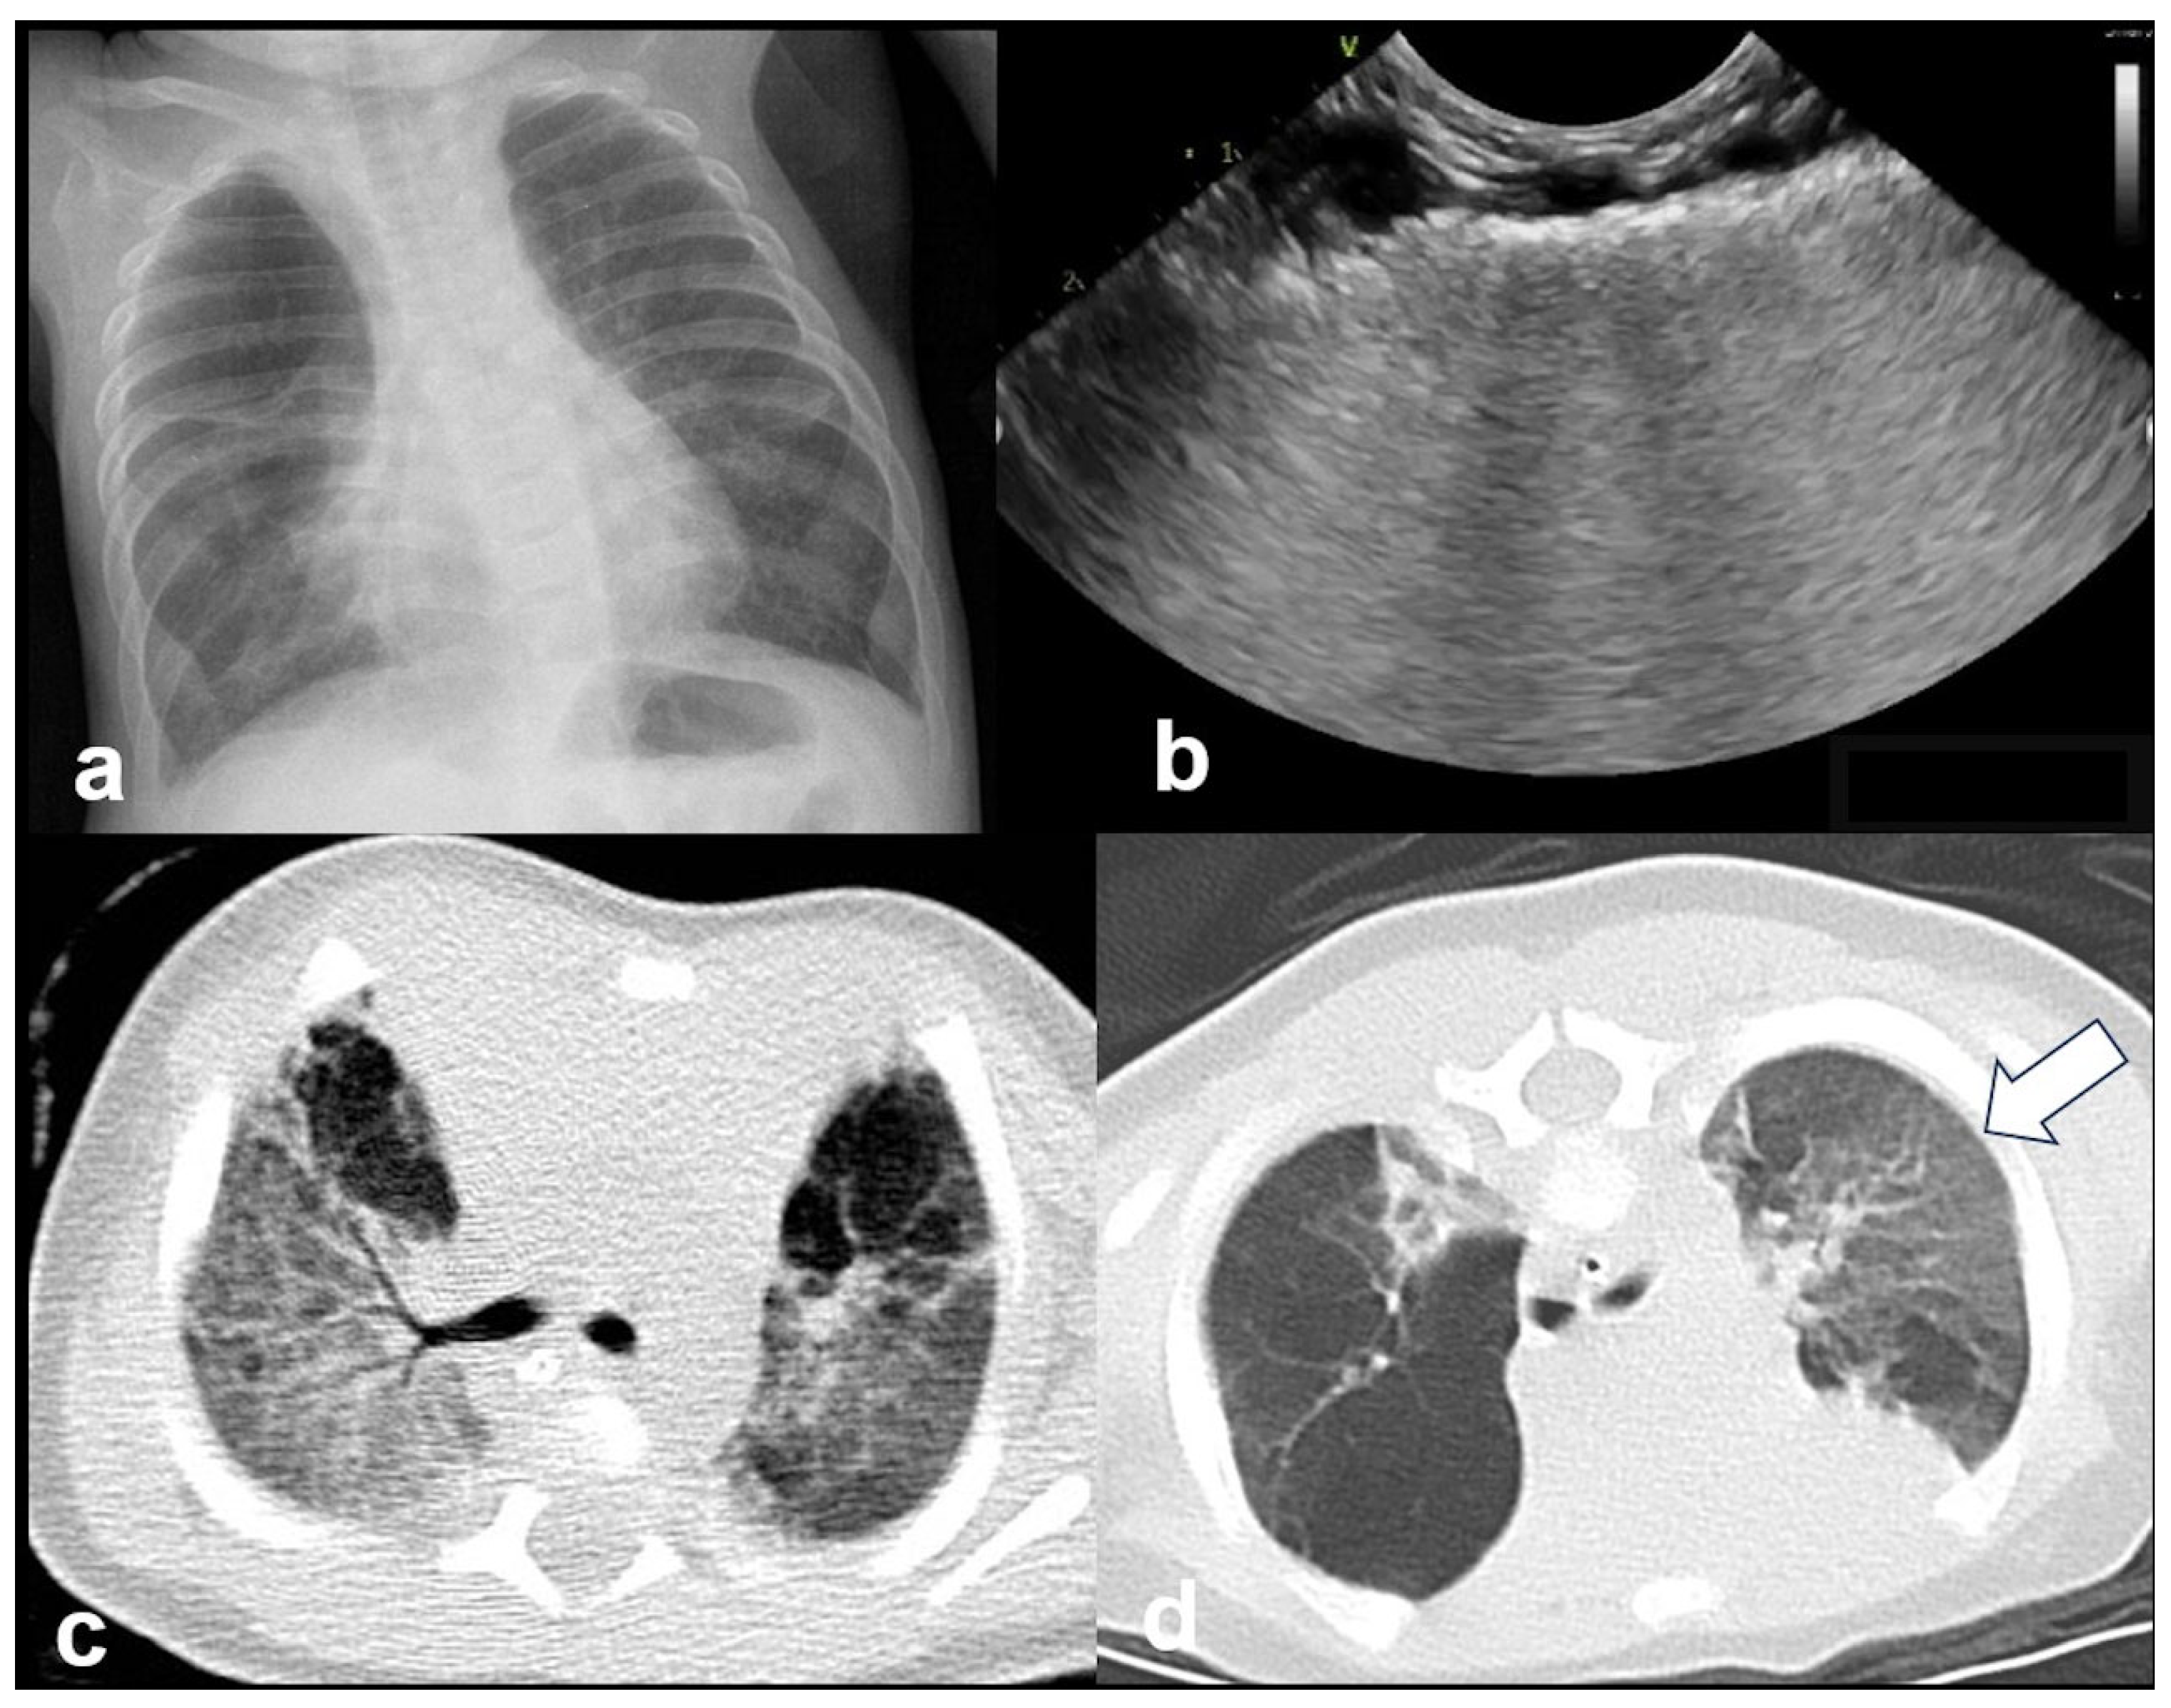

3.2.6. Bronchopulmonary Dysplasia (BPD)

BPD is a chronic lung disease primarily affecting preterm infants who required prolonged mechanical ventilation or oxygen therapy. LUS findings in BPD often reveal an abnormal distribution of aeration patterns, reflecting heterogeneous pulmonary involvement. One of the hallmark features of BPD is the presence of areas with “solid” or coalescent B-lines, indicating interstitial fibrosis or chronic lung remodeling. In addition, the pleural line may appear to be abnormally thickened and irregular, which is consistent with chronic inflammation and structural alterations to the lung periphery. Subpleural thickenings of varying sizes can also be seen scattered throughout the lung fields, representing localized fibrosis or areas of reduced aeration (Figure 18 and Figure 19).

Figure 19.

Bronchopulmonary dysplasia: (a) CXR; (b) LUS: abnormal thickening of pleural line; (c,d) CT. The main findings from all methods include lung parenchymal changes unequally distributed and contiguous to spared areas (arrow in (d)).

Taken together, these findings, coupled with a history of prolonged mechanical ventilation, provide a non-invasive method of assessing the severity and progression of BPD in neonates and can assist in differentiating it from acute respiratory conditions [16,20,47].